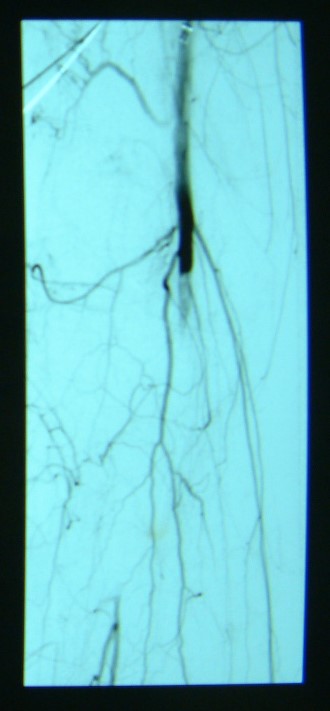

急性下肢動(dòng)脈缺血

治療前

治療后